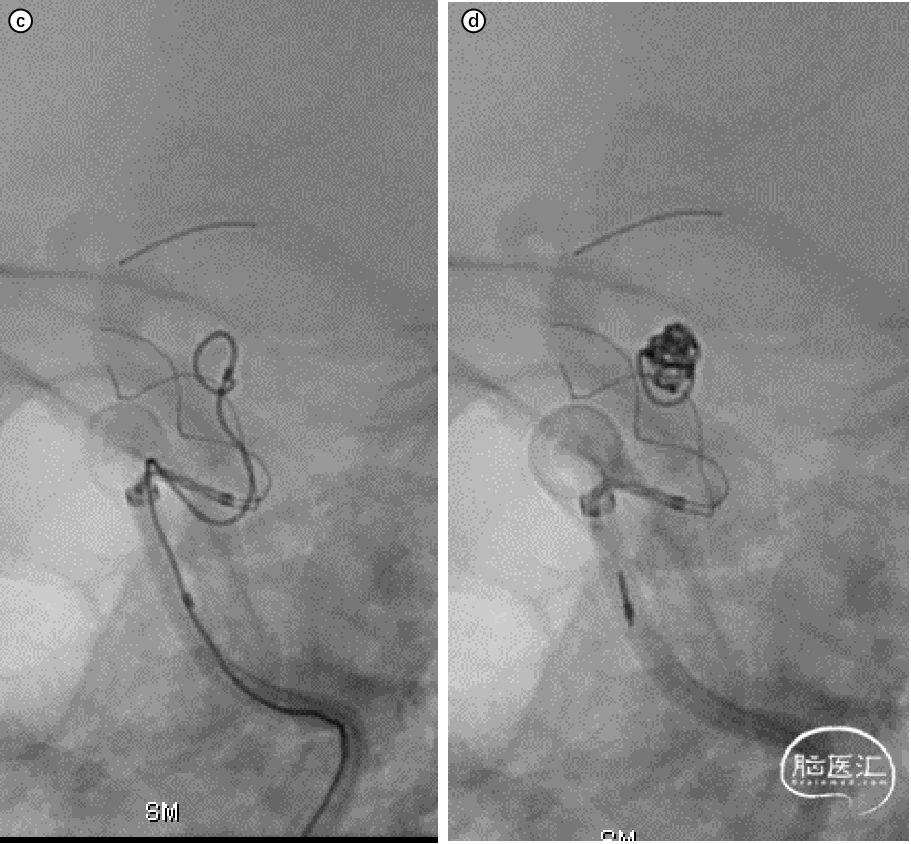

图3:栓塞完毕,支架解脱后造影,动脉瘤不显影。

图4:支架末段卸张力释放,造影提示贴壁欠佳(红色箭头)。

考虑到支架近端已经完全打开,此时可以采用微导丝微导管按摩来让支架完全贴合血管壁。